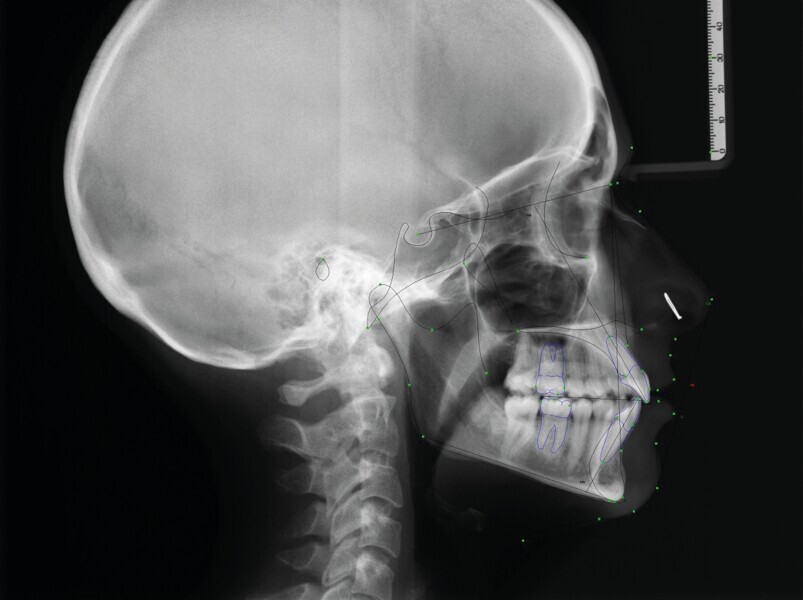

Fig. 8a : radiographie céphalométrique initiale

Fig. 8b : radiographie céphalométrique finale.

La radiographie panoramique finale (Fig. 7) montre des racines parallèles et l’absence de tout signe de résorption radiculaire (bien que seules des radiographies périapicales pourraient confirmer ceci). Selon l’analyse céphalométrique, les incisives maxillaires et mandibulaires ont conservé leur position (position initiale de l’incisive mandibulaire à la ligne A-pogonion (A-Pog) : 14 mm ; position finale de l’incisive mandibulaire à la ligne A-Pog : 13 mm. Fig. 8 )